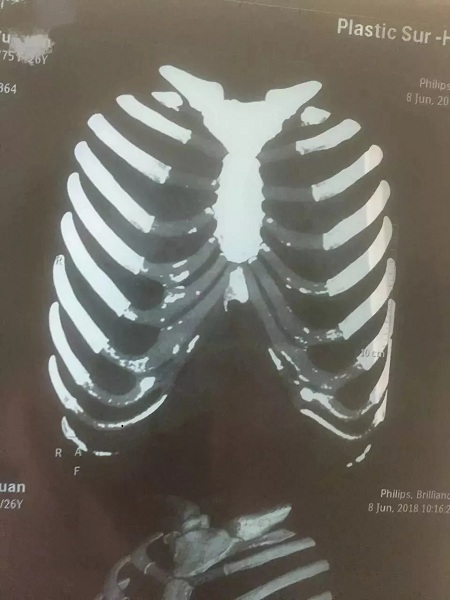

▼鈣化肋軟骨和未鈣化肋軟骨的影像區別

如上圖所示,鈣化了的肋軟骨和硬骨一樣,都是呈同樣密度的白色顯示,而正常的肋軟骨密度顯示是透明狀。

輕微鈣化的肋軟骨不會影響隆鼻效果,不過對醫師的雕刻技術是一個考驗。

▼輕微鈣化的肋軟骨